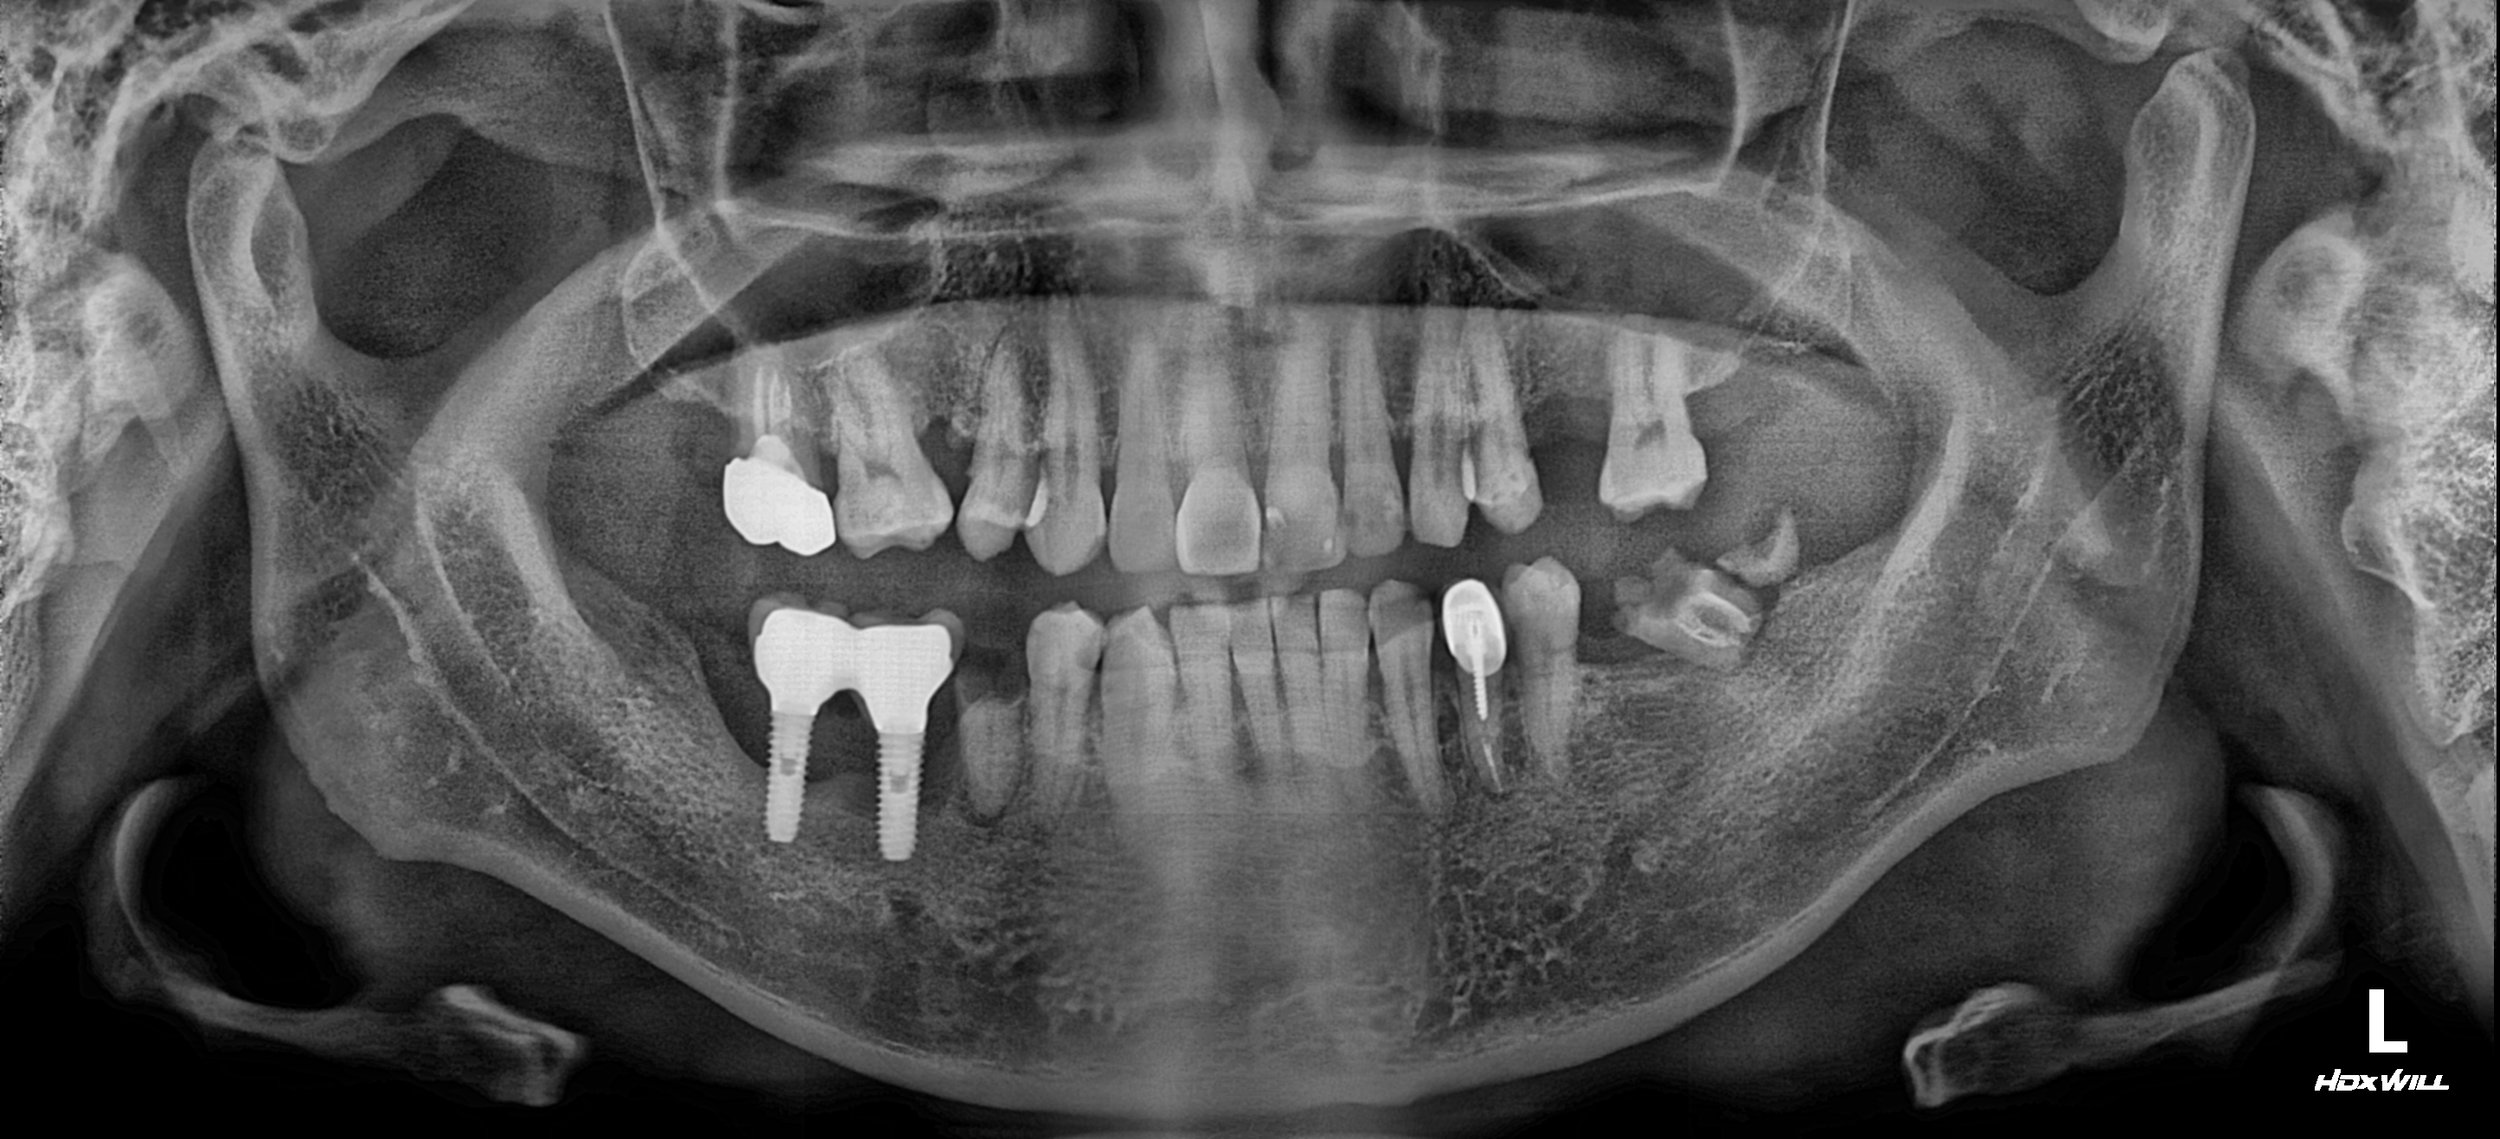

35. Comprehensive Full-Arch Transformation: Restoring Confidence in a Young Phobic Patient

Reversing the effects of generalized rampant caries and occlusal collapse in a female patient in her 20s. A tooth-preserving, implant-assisted approach focused on stable VDO elevation and overcoming social anxiety.